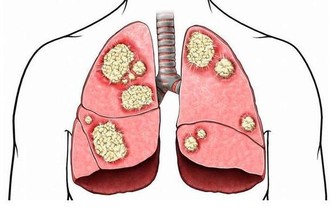

過敏性鼻炎不僅表現為一些打噴嚏、流鼻涕、鼻塞的鼻部症狀,

如果不積極做好防控,還可能會引起其他相關疾病,

如黑眼圈、眼睛瘙癢、鼻子瘙癢、蕁麻疹、濕疹,長期不治療,還可能會導致過敏性哮喘

醫學資料顯示,約10%左右的過敏性鼻炎患兒,有可能發展為哮喘患者;

而患哮喘的孩子中,同時患有鼻炎是個很常見的問題。

鼻子是我們夜間呼吸的主要通道,一旦鼻腔因為鼻炎發作,出現腺樣體肥大,

導致進入鼻腔的氣流受限,病人氣道通氣量減少,出現機體的慢性缺氧。